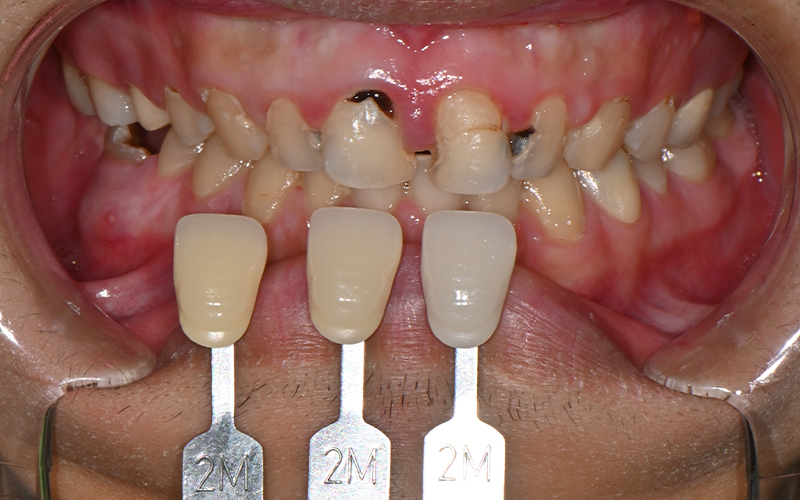

The patient we are introducing had several cavities in progress,

and the pain would come and go,

which made it even easier to miss the right timing for treatment.

As can actually be seen in the treatment record,

more than 10 teeth received

root canal treatment,

and most were accompanied by complex inflammation and nerve infection.

Because the front teeth are also an area that is visually noticeable,

the plan was carefully considered.

Before treatment, we also checked the tooth color

using a shade guide.